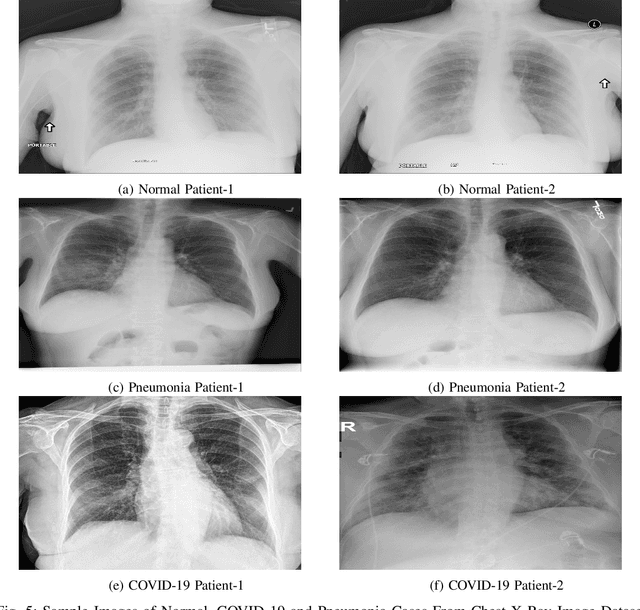

Abstract:Early identification of COVID-19 using a deep model trained on Chest X-Ray and CT images has gained considerable attention from researchers to speed up the process of identification of active COVID-19 cases. These deep models act as an aid to hospitals that suffer from the unavailability of specialists or radiologists, specifically in remote areas. Various deep models have been proposed to detect the COVID-19 cases, but few works have been performed to prevent the deep models against adversarial attacks capable of fooling the deep model by using a small perturbation in image pixels. This paper presents an evaluation of the performance of deep COVID-19 models against adversarial attacks. Also, it proposes an efficient yet effective Fuzzy Unique Image Transformation (FUIT) technique that downsamples the image pixels into an interval. The images obtained after the FUIT transformation are further utilized for training the secure deep model that preserves high accuracy of the diagnosis of COVID-19 cases and provides reliable defense against the adversarial attacks. The experiments and results show the proposed model prevents the deep model against the six adversarial attacks and maintains high accuracy to classify the COVID-19 cases from the Chest X-Ray image and CT image Datasets. The results also recommend that a careful inspection is required before practically applying the deep models to diagnose the COVID-19 cases.